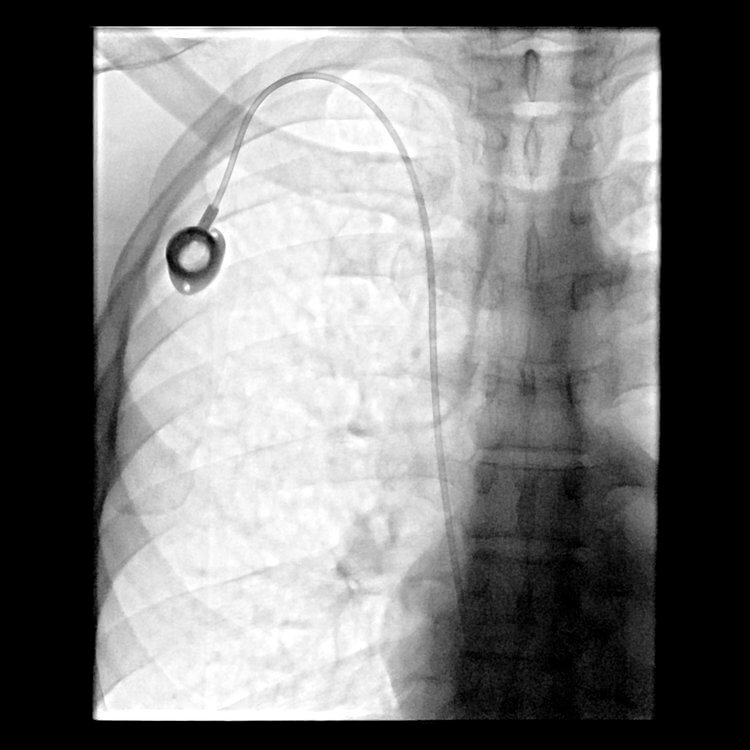

Venous Access

Cancer patients often require venous access to enable them to receive intravenous medications for treatment and to undergo frequent blood draws for follow-up testing. For these patients, IR plays a significant role in their care by placing one of a number of different venous access devices. These include PICC lines, ports, and other tunneled central lines. The image-guided techniques used in IR insure that these devices are placed appropriately and are immediately available for use once the procedure is completed.